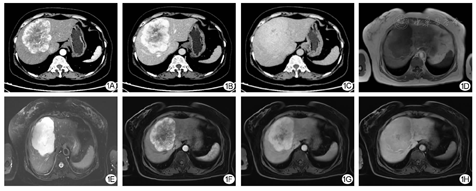

患者女性,59岁。主因"查体发现肝占位1周"于2020年8月6日入住天津市第一中心医院。既往无饮酒史及长期用药史。入院后查腹部增强CT提示肝左右叶交界处(Ⅳ、Ⅷ段)富血供肿物(图1A,图1B,图1C)。进一步查普美显增强MRI提示肝左右叶交界处(Ⅳ、Ⅷ段)富血供肿物,不含功能肝细胞,考虑血管肉瘤可能(图1D,图1E,图1F,图1G,图1H)。患者于2020年8月在全麻下接受肝部分切除术,术中可见肝Ⅴ、Ⅷ巨大肿物,质软。完整切除的肿物切开后可见肿物切面呈白实性。

根据Tao等[6]报道,AH的CT平扫多表现为边界清晰的等或稍低密度类圆形不均质肿物,轮廓分明;在增强CT扫描的动脉期,病灶边缘可表现出明显的环形和结节状强化,静脉期病灶会进一步增强,而延迟期图像上则显示出均匀持续增强。本例患者肿物的增强CT与上述表现基本一致,普美显增强MRI则表现为动脉期可见明显不均匀周边强化,门脉期及静脉期可见强化向内充填。可见肝AH的影像学表现与海绵状血管瘤及血管肉瘤相似,由于目前报道的病例数较少,尚没有关于此病统一的影像学诊断标准。由于无法排除海绵状血管瘤,因此肝穿刺活检仍需慎重。本例患者术中可见肿瘤与周围正常肝组织界限清楚,有不连续包膜存在,因此手术以肿瘤局部切除为主,切缘距肿瘤边缘1 cm以上为宜。目前尚没有该肿瘤接受介入治疗及药物治疗的相关研究报告。